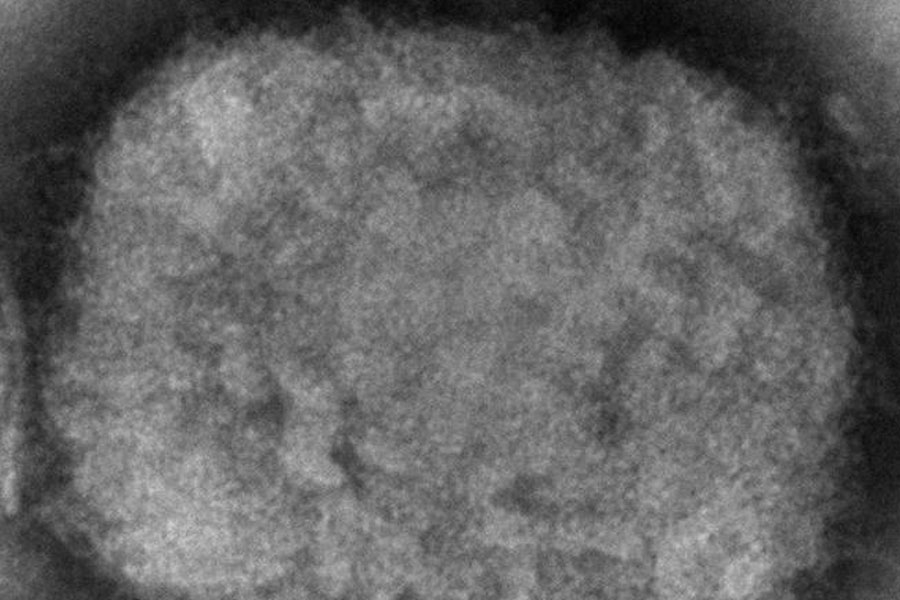

Nueva York, EE.UU. — Massachusetts reportó el miércoles un raro caso de viruela símica en un hombre que viajó recientemente a Canadá, y los funcionarios de salud están revisando si está relacionado con pequeños brotes en Europa.

La viruela símica suele limitarse a África, y los raros casos que se dan en Estados Unidos y otros países suelen estar relacionados con viajes a ese continente. Este mes se ha notificado un pequeño número de casos confirmados o sospechosos en Gran Bretaña, Portugal y España.

La viruela símica suele comenzar con una enfermedad similar a la gripe y una inflamación de los ganglios linfáticos, seguida de erupciones en la cara y el cuerpo. En África, la gente se ha infectado a través de las mordeduras de roedores o pequeños animales, y no suele propagarse fácilmente entre las personas.

La viruela símica pertenece a la misma familia de virus que la varicela. La mayoría de las personas se recuperan de la viruela símica en unas semanas, pero la enfermedad es mortal para hasta una de cada 10 personas, según la Organización Mundial de la Salud.